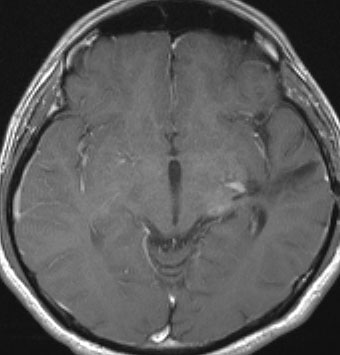

10才の時に,複雑部分発作(症候性てんかん)で発症しました。吐き気を感じた後に嘔吐して意識が遠くなる(意識減損)という症状であり,側頭葉てんかんです。脳波では左側頭葉に徐波律動がみられました。発作は頻回でしたがカルバマゼピンの投与で抑制されていましたが,MRIで腫瘍が発見されました。

左内側側頭葉グリオーマ mesial temporal glioma と呼ばれる腫瘍です。左の扁桃体,海馬鉤,海馬,海馬傍回に腫瘍が浸潤しています。T2強調画像とFLAIRでまだらな高信号で境界ははっきりしません。mass effectが少なく,増殖増大傾向のある腫瘍には見えないのが特徴です。下段右のように部分的にガドリニウム増強されるのも神経節細胞腫の特徴かもしれません。しかし,神経節膠腫,乏突起膠腫,乏突起星細胞腫(グレード2)なども疑われます。

手術中の脳波モニターでは,棘波が上側頭回の後方(ウェルニッケ領域)に存在し,深部電極刺入で海馬近傍にも棘波がみられましたが,もちろん上側頭回や海馬の切除はしませんでした。扁桃体 amygdala と海馬鈎 uncus の腫瘍部分のみを切除して手術を終了しています。海馬と海馬傍回には腫瘍を残しました。上のMRIは,その後6年経過した後のものですが腫瘍は全く同じ大きさです。抗てんかん薬も止めて,発作は全く生じていません。このような腫瘍は,扁桃体と海馬鉤を摘出することで,発作を完全に止めることができることがあります。ですから,最初の手術では,リスクのある余分な脳切除をしません。